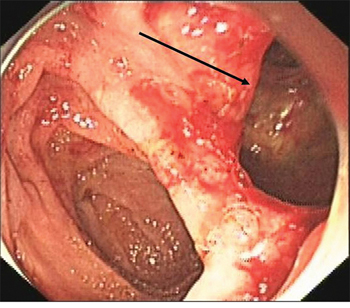

A 49-year-old female was admitted for persistent abdominal pain and fever of 1 week’s duration. MRCP showed multiple common bile duct stones with accompanying duct dilatation. After admission, antibiotics were administered and ERCP was performed the following day. After successful intubation, ERCP revealed choledochectasia with multiple stones (maximum diameter 1.6 cm × 1.5 cm). After routine EST, papillary sphincter dilatation was performed. Due to the larger size of the stones, lithotripsy and a stone-removal basket (Boston Scientific, Marlborough, MA, USA) were used to break and extract the stones. Repeat cholangiography demonstrated no residual stones; however, abnormal perinephric gas shadowing was observed (Figure 1). Under the duodenal endoscopy, an approximately 2.0 cm × 1.5 cm perforation was visualized on the lateral duodenal wall, with visible retroperitoneal loose connective tissue (Figure 2). We suspected that because the stone basket was over-rigid, it could have penetrated the contralateral intestinal wall due to inertial forces during stone removal.

Figure 2: Retroperitoneal loose connective tissue (arrow), viewed endoscopically.